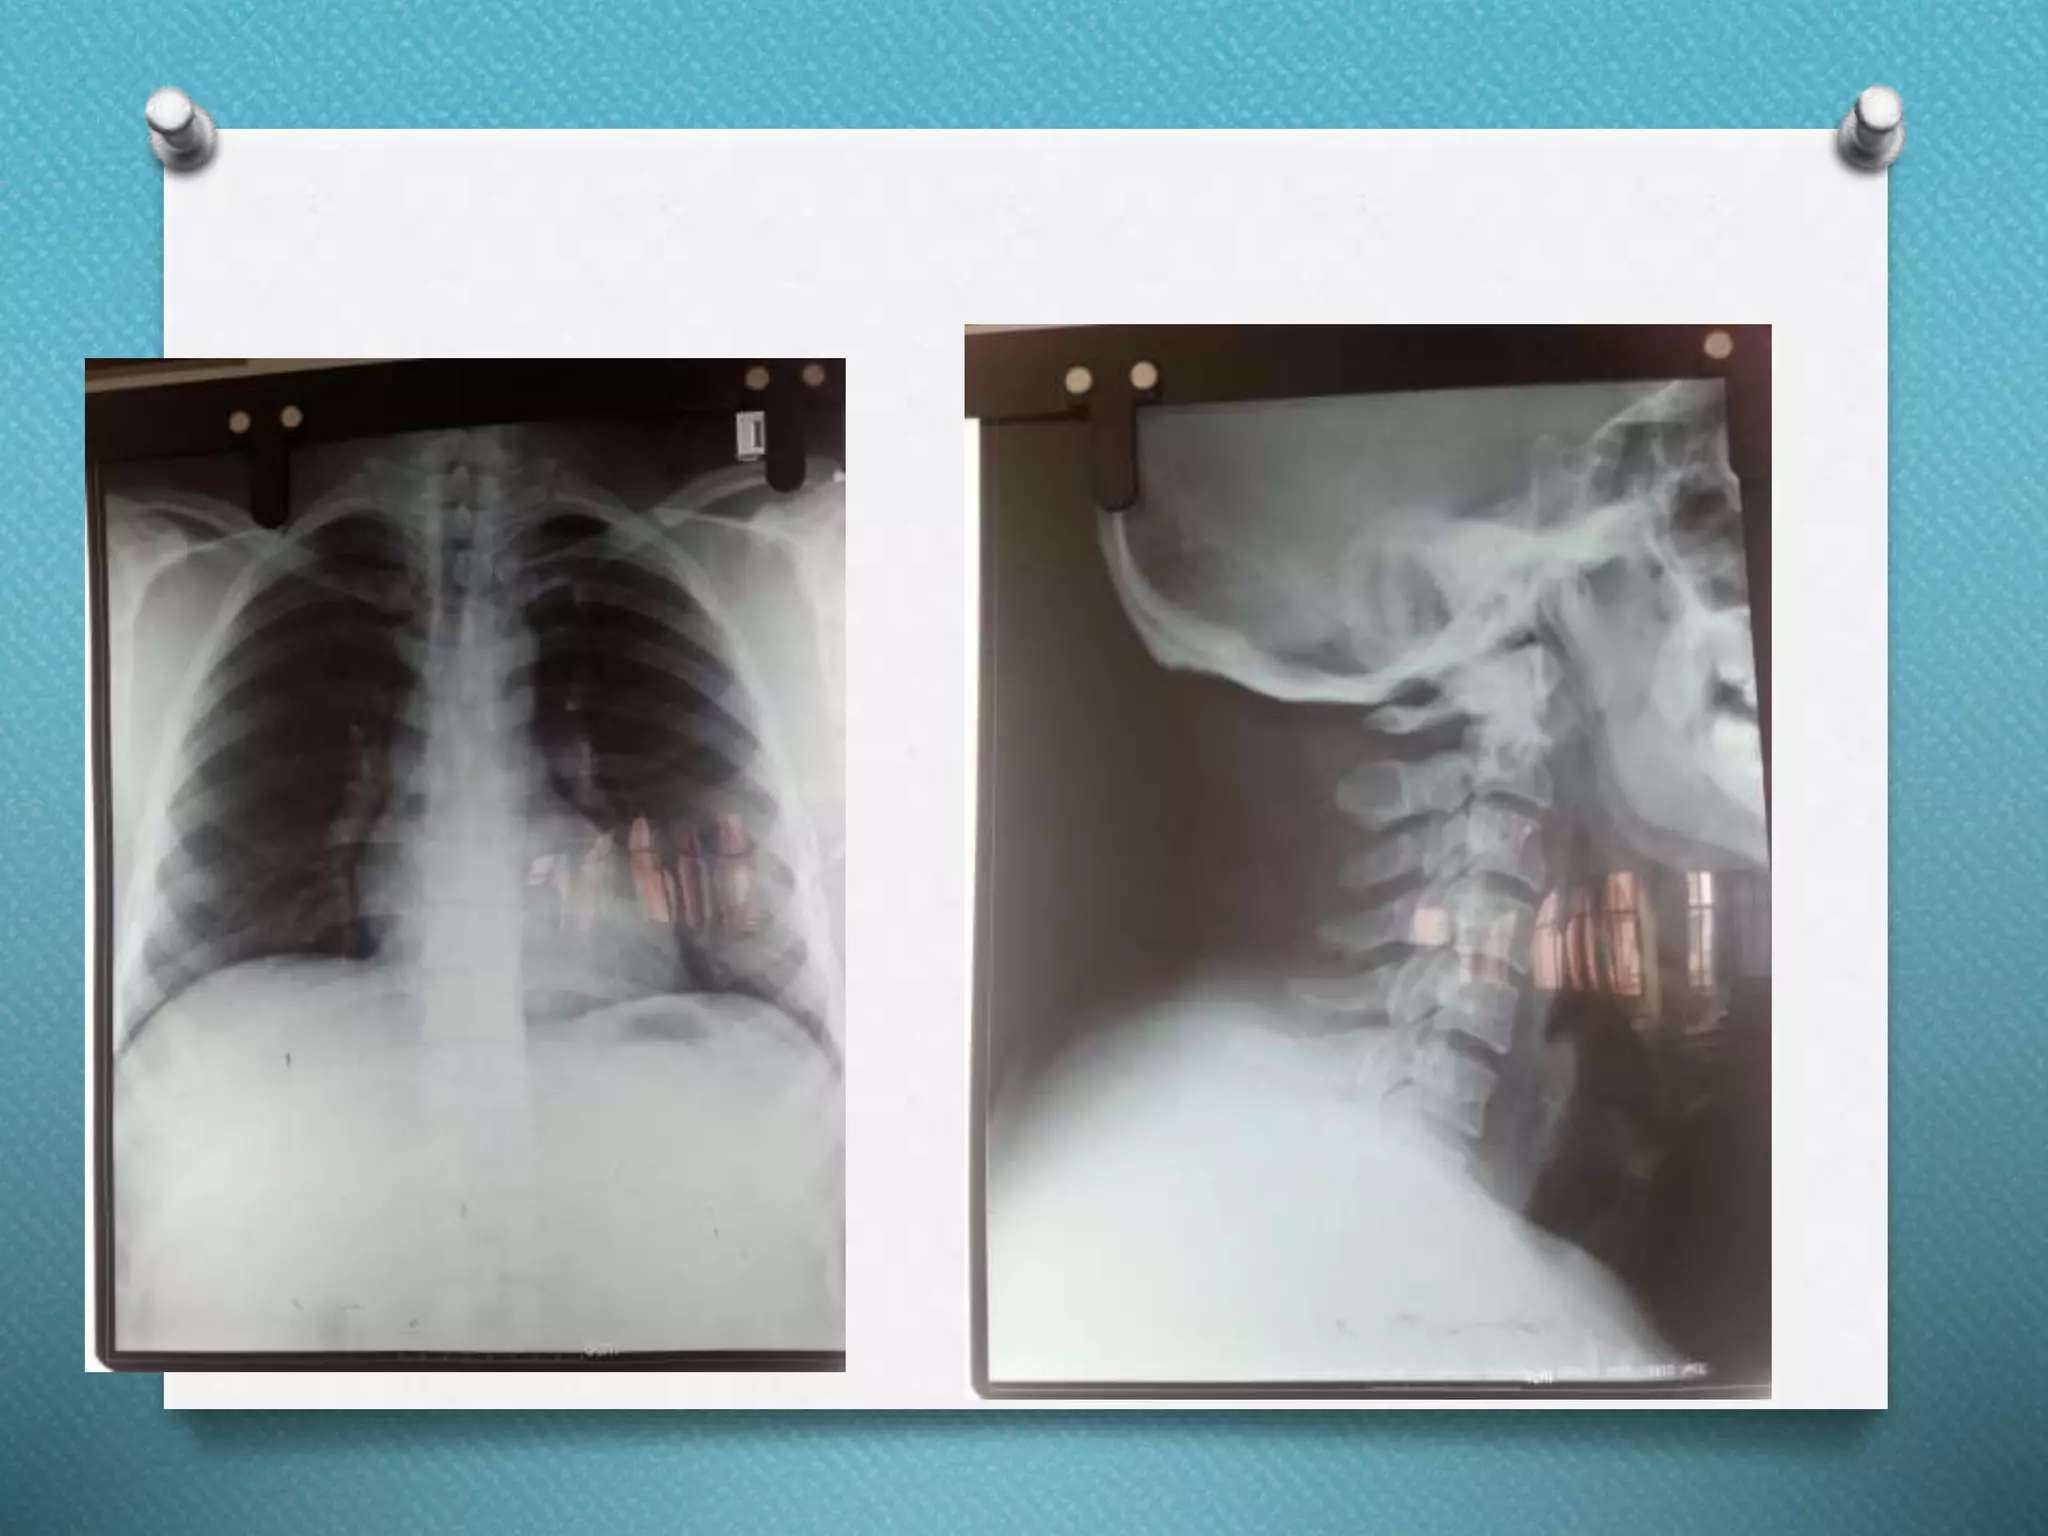

RAD

Investigations O Hb:13.2 gm% OTC: 10,300/mm3 O P72, L22, E06 O PT: 15 secs O INR: 1.1 O Platelets: 2,25,000/mm3 O Blood group: 0 +ve O Na: 146 meq/l O K: 4.7 meq/l O Urea: 26 mg/dl O Creatinine: 0.9 mg/dl O RBS: 134 mg/dl O ABG: N/A O Trop I – Neg O CK MB- 17 U/L

O Normal echocardiographicfindings LVEF-65% O Normal Thyroid function tests T3= 2.63 pg/L T4= 11.49 pg/L TSH= 1.10 mIU/L